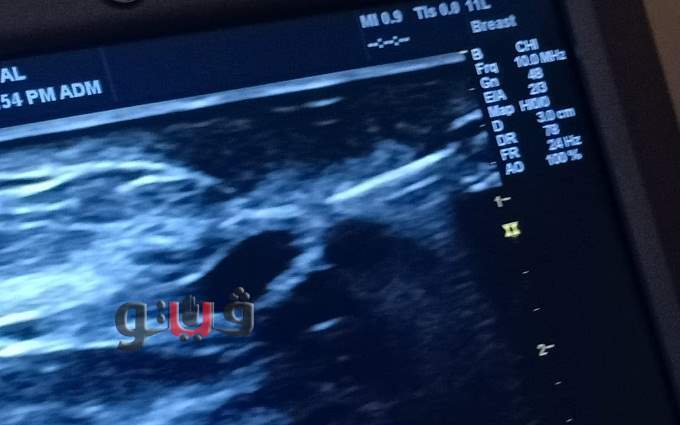

وجاء ذلك ضمن المبادرة الرئاسية لدعم صحة المرأة والكشف المبكر عن سرطان الثدي، بعد عمل الفحوصات المعملية والأشعات اللازمة، ومنها أشعة "الماموجرام" علي الثدي.

كما قام الفريق الطبي بمستشفي فاقوس النموذجي بتقديم الخدمة الطبية للسيدات بمبادرة صحة المرأة، بعمل فحص إكلينيكي متقدم وأشعة سونار لنحو٧٦ سيدة، بعد إحالتهم من العيادات الطبية للمبادرة بمختلف أنحاء المحافظة، لتلقي العلاج بالمستشفي.